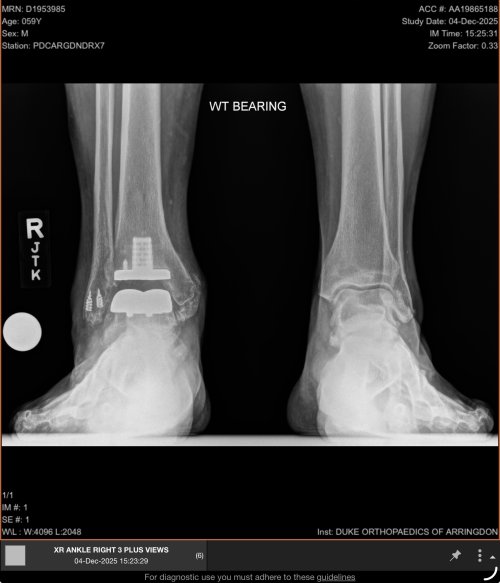

On Sunday I stepped off my horse wrong after roping a run back calf in the morning and sprained my ankle good. Worked the rest of the day on horseback and ran the ancient squeeze chute for 48 head. Drove home 2 hours and made a doctor appointment at urgent care on Monday.

Well after a quick exam and in house X-rays they showed me a spiral fracture just above the distal end of the fibula.

Got an orthopedic appointment next week and a new walking boot. This is the first time I’ve ever been on crutches in my 51 years.

IMG_5912.jpeg

Well now what? Any thoughts from others who have dealt with this?